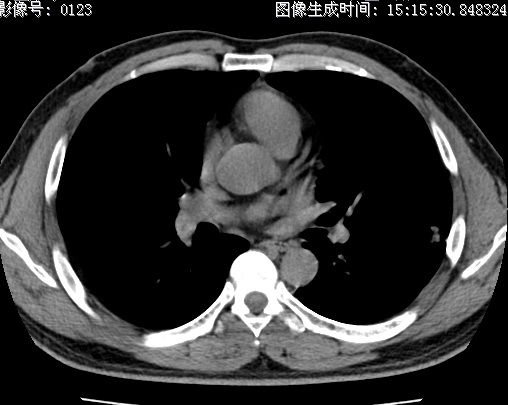

以下是引用zhao_bin2008在2010-1-4 20:15:00的发言:[br]先天性肺囊肿或小的肺隔离症?

以下是引用卜一在2010-1-4 22:09:00的发言:[br]先天性肺囊肿或小的肺隔离症?支持!

以下是引用zsl6918在2010-1-5 5:23:00的发言:[br]良性改变!肺囊肿,先天性支气管闭锁,血管畸形等均有可能。

以下是引用影像之路在2010-1-6 11:10:00的发言:[br]腺癌,最终的病检有些出乎意料之外,术前同志们大多考虑为肺囊肿或小的肺隔离征 [br]回过头来看 小结节呈分叶状,其内侧有一条较粗的静脉供血或许能成为支持诊断腺癌的理由